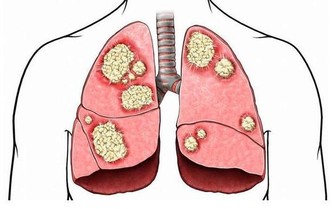

大腸癌為結腸癌和直腸癌的總稱,大腸癌是指大腸粘膜上皮在環境或遺傳等多種致癌因素作用下發生的惡性病變預後不良,死亡率較高。

大腸癌是大腸粘膜上皮起源的惡性腫瘤。

是最常見的消化道惡性腫瘤之一。